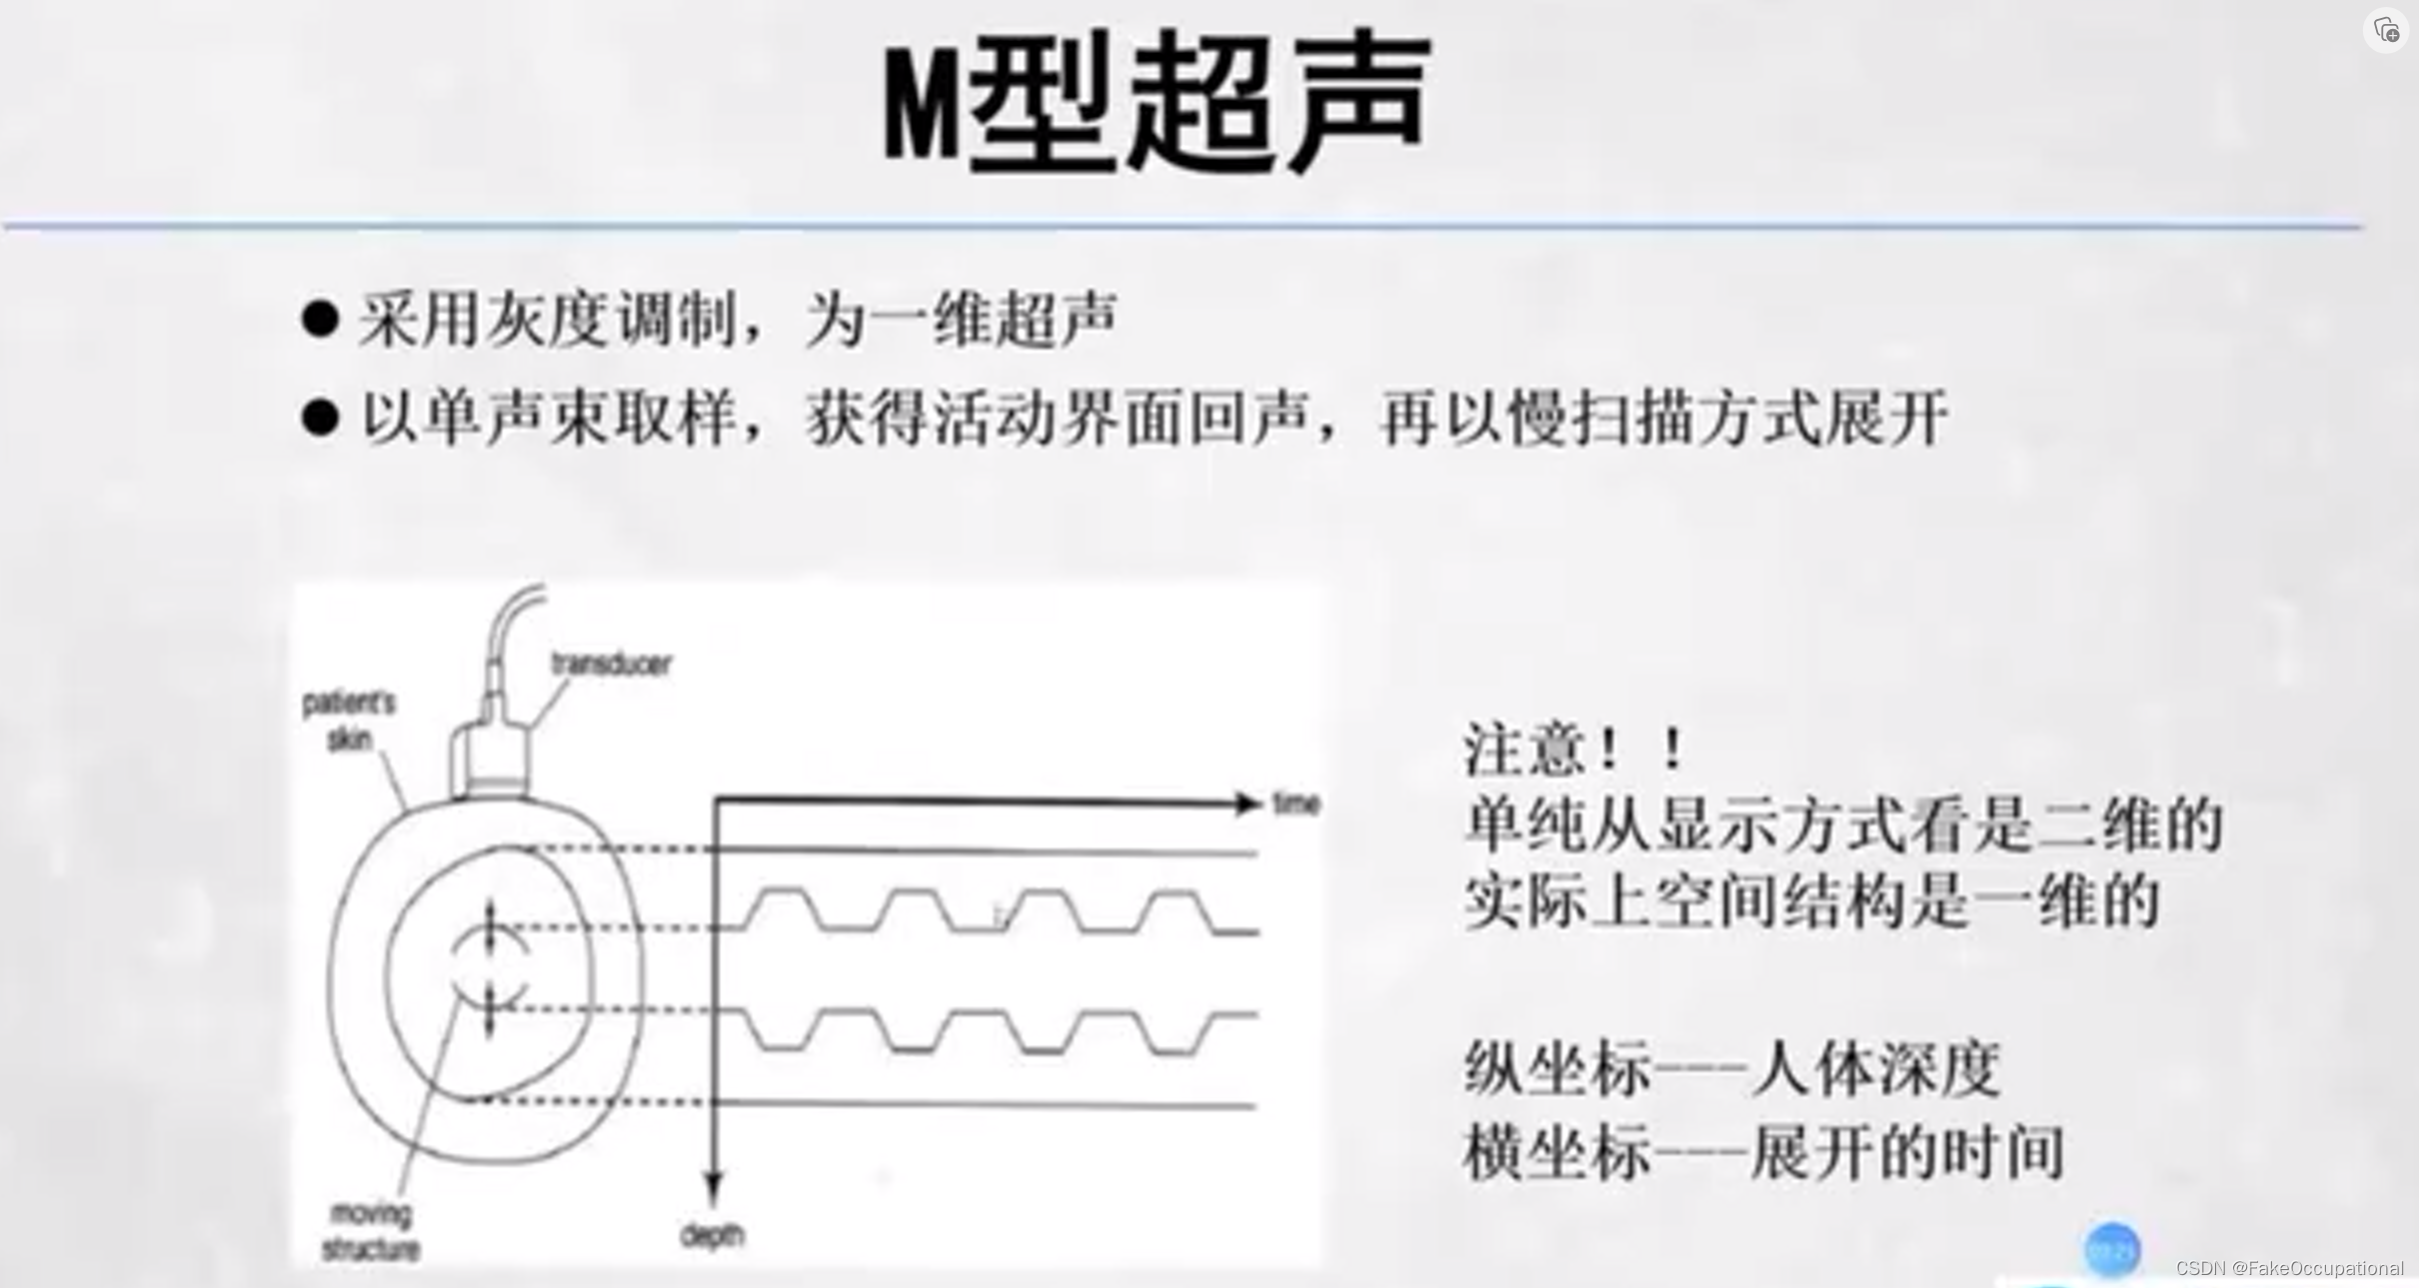

超声成像方法包括A型,B型,M型,D型(频谱多普勒,多普勒血流成像)。